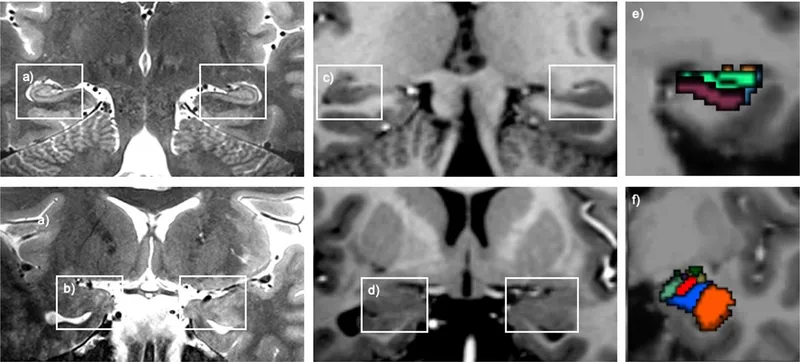

- Brain Structural & Functional Changes: ↓ Hippocampal volume; altered Prefrontal Cortex (PFC), amygdala, Anterior Cingulate Cortex (ACC) activity.